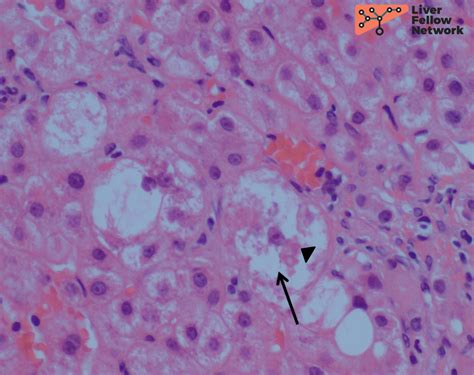

- mallory hyaline bodies

- mallory denk bodies liver histology

- mallory denk bodies liver

- mallory denk bodies histology

- mallory bodies histology

- mallory bodies liver biopsy